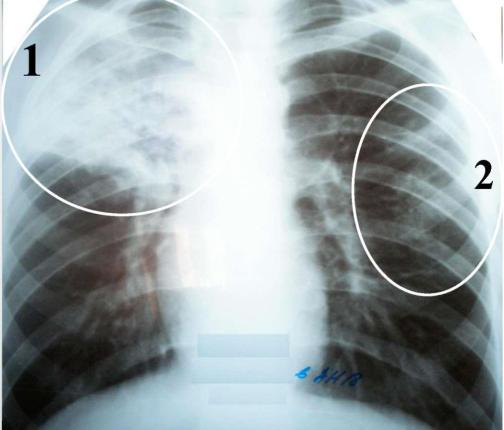

Иллюстрации по теме очагового и инфильтративного туберкулеза